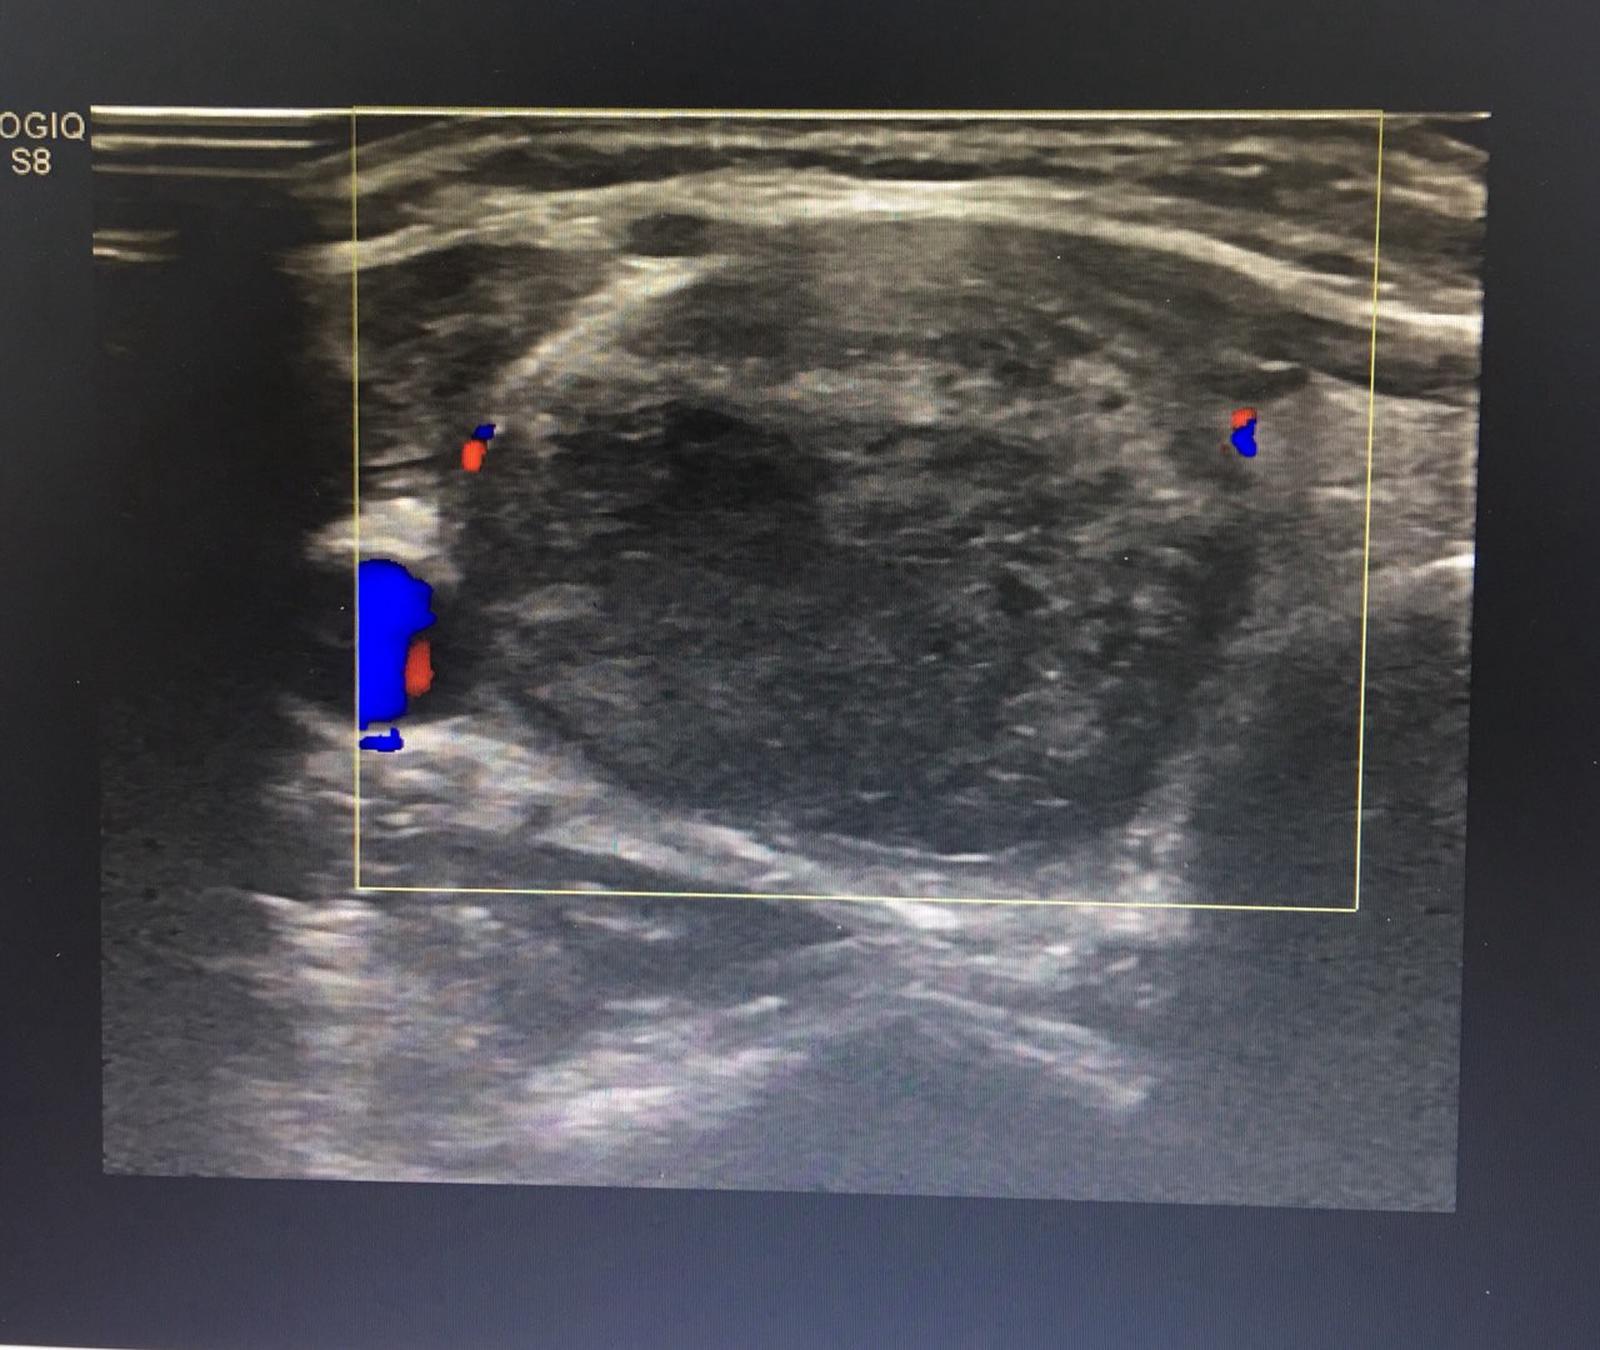

Hình ảnh khối u giáp thể tích 13mm3, đường kính 36mm

Hình ảnh khối u giáp sau khi đốt sóng cao tần không còn mạch máu nuôi u